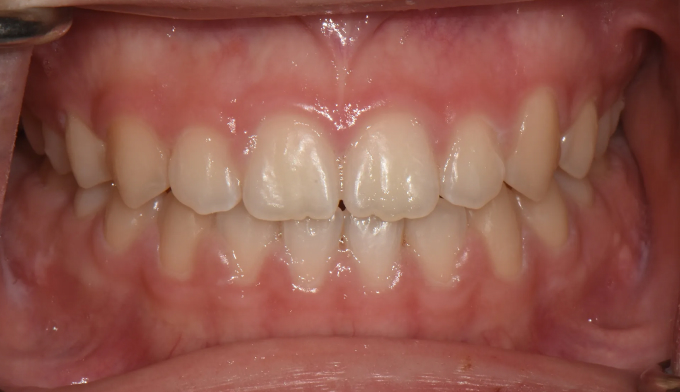

개방교합은 좋지않은 발음을 만들기도 하지만 심미적으로도 좋아보이지 않아서 교정치료를 받으러 많이 오십니다. 치아는 가지런하므로 교정치료가 어렵지 않아 보이지만 개방교합의 치료는 교정용 미니스크류의 식립도 필요하며, 재발도 잘되는 어려운 교정입니다. 교정치료 이후에 재발되지 않게 주기적인 관리 및 연습도 필요합니다.

어금니의 미니스크류의 식립을 통하여 개방교합을 치료하였습니다. 총 치료기간은 13개월입니다.